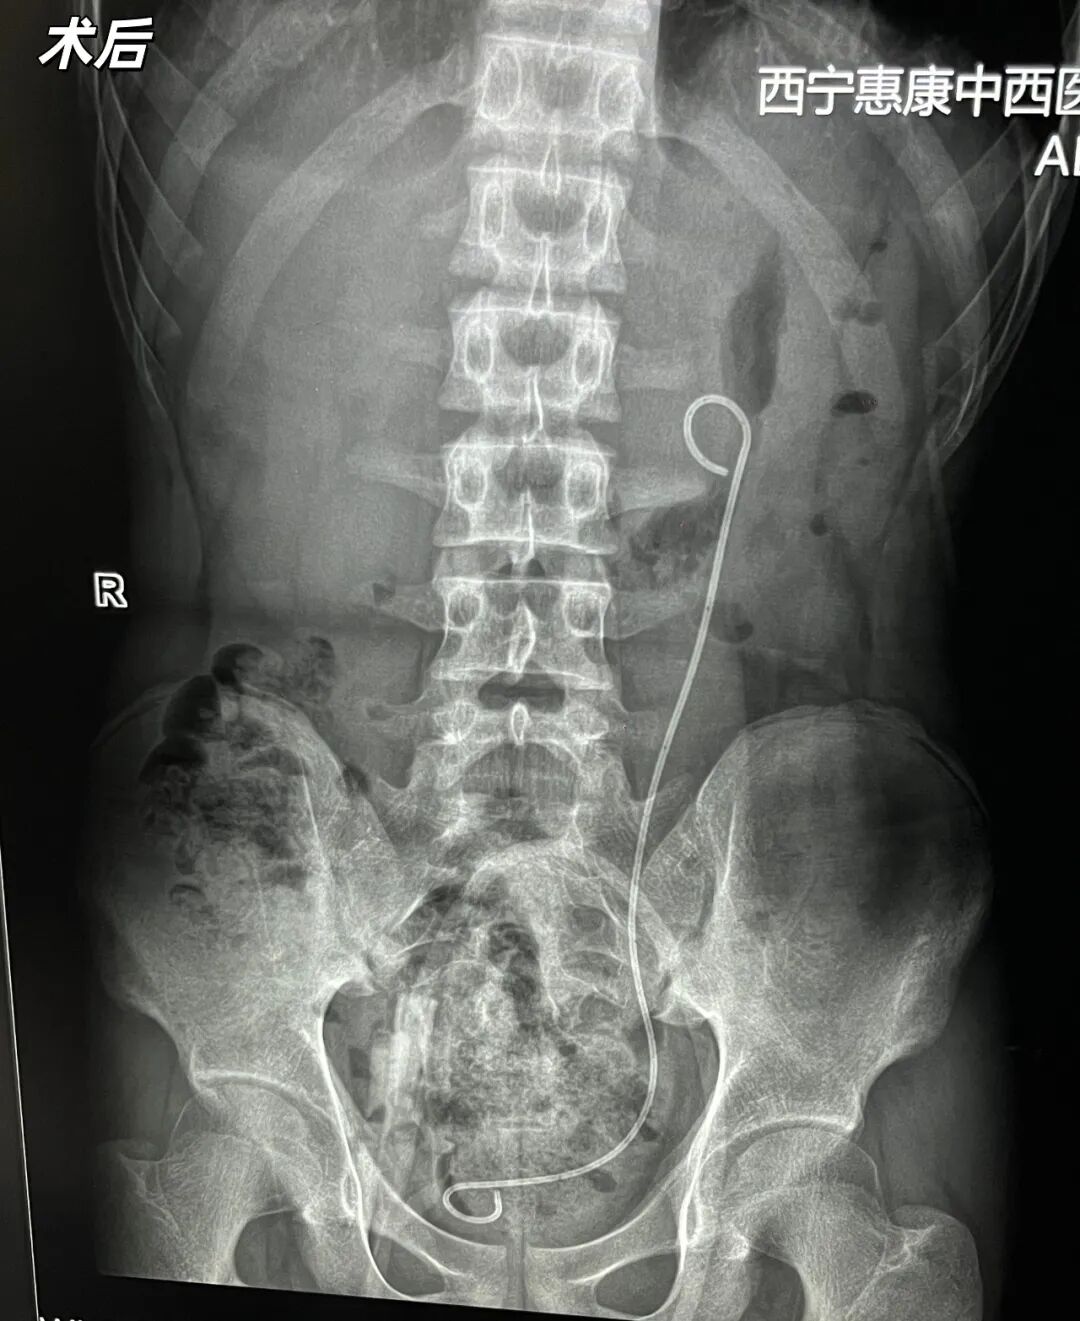

在此关键时刻,手术团队再次发挥集体智慧,秉持“安全第一、有效治疗”的原则,迅速调整手术策略。考虑到结石位于中上盏,位置特殊,而软镜具有可弯曲、能灵活调整角度的特性,能够更好地在变形的肾盂内“转弯”,既能有效规避损伤胸膜的风险,又能精准到达结石所在位置。经紧急商议,团队决定在此基础上申请并启用软镜,以经皮肾镜穿刺定位结合软镜碎石的方案进行手术。

这一灵活的战术调整立竿见影。软镜凭借其可弯曲的优势,顺利到达了肾镜无法触及的肾中上盏区域,精准地锁定了结石。在清晰的可视化操作下,顺利完成碎石取石操作。整个手术过程出血量少,未对周围组织器官造成副损伤。

术后恢复良好

在医护团队的精心照护下,术后患者病情平稳,逐步康复。此次经皮肾镜+软镜双结合手术的成功,是我院外科团队针对复杂病例开展个体化诊疗的一次实践,也彰显了我院外科团队面对突发情况时灵活应变、以患者安全为核心、敢于优化方案的担当精神。我院将继续秉承精益求精的工匠精神,不断提升医疗技术和服务水平,为更多患者的健康保驾护航。